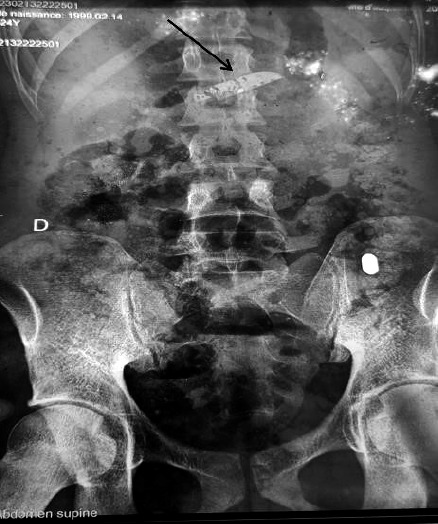

Case report: We present the successful management of the consequences of voluntary knife ingestion in a 24-year-old male with undocumented psychiatric disorders. The patient was admitted to the emergency department with a fistulized epigastric skin abscess, with the tip of a knife protruding from it. This extraordinary case involved the migration of an ingested knife, which perforated the stomach and externalized through an epigastric abscess. Surgical removal of the foreign body was performed.

Discussion: Several hypotheses explain the ingestion of the knife in a person with psychiatric disorders, including self-mutilation, the pernicious mystical influence of malevolent third parties, or self-administration of a neomystical ritual.

Conclusion: The development of a skin abscess secondary to foreign body ingestion is rare but should be considered in the absence of other causes.